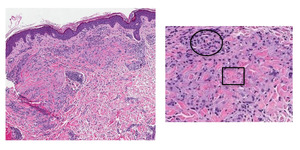

One condition that tends to be recognized by PCPs is granuloma annulare (GA), which involves a benign accumulation of macrophages called a “granuloma” in the skin’s dermis.6 This condition typically occurs in children under the age of 10 and adults over the age of 40, and affects women twice as often as men.6 GA often presents as elevated, small (i.e., “papular”) and/or large (i.e., “plaque”) red lesions in ring-like (i.e., “annular”) formations on the trunk and/or extremities (Figure 1).6

Patch GA is a unique clinical variant of GA, with smooth erythematous-to-brown patches on the trunk and/or extremities, as opposed to red papules or annular plaques.6,8 It is diagnosed most frequently in females over age 50.6 While the annual incidence and prevalence of GA is approximately 0.1% to 0.4%, the number of cases of patch GA presenting to PCPs and even dermatologists are far less.6,9 For example, an institution-based, 10-year review of a dermatopathology database (2009-2019) determined 23 out of 108 (21.3%) potential histologic cases resembling GA to be specifically of the patch variant.10

On physical exam, several red-brown patches were present on the bilateral flanks, buttocks, posterior thighs, anterior thighs, abdominal skin folds, and the back of her knees (i.e., “popliteal fossae”). There were scattered pink papules on her posterior shoulders, elbows, and ventral wrists, too. On her wrists, some of the papules coalesced to form plaques (see Figure 2).